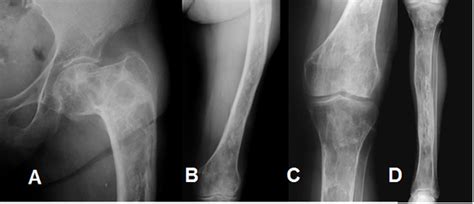

La transformación maligna en la displasia fibrosa es poco frecuente, y las tasas de malignización son de un 0,5% para la variante monostótica y del 4% para la variante poliostótica asociada al síndrome de McCune-Allbright.

Se produce transformación maligna a sarcoma en un porcentaje muy bajo de pacientes (0,4% en DF monostótica y hasta un 4% en McCune Albright). La región craneofacial es el lugar de malignización más frecuente, con 35,6% de conversión (vs. en el fémur que tiene una frecuencia del 24,7% o en la tibia con frecuencia del 12,8%). A pesar de la creencia de que factor de riesgo más importante para que ocurra es la radiación previa, no es estrictamente necesaria, como demostraron Schwartz y Alpert en 1964.

La degeneración neoplásica es muy infrecuente (0,5%) y, curiosamente, en un tercio de los pacientes se han descrito antecedentes de radiación. Puede ocurrir en ambas formas, mono y poliostótica, siendo las transformaciones más frecuentes a osteosarcoma, fibrosarcoma y condrosarcoma, en orden decreciente. Debe sospecharse ante un incremento del dolor o de la tumoración o ante un cambio radiológico significativo respecto a densidad y/o extensión de la tumoración.